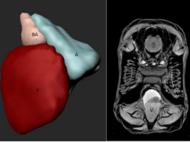

Imaging Platform

The central imaging core facility at the MPI for heart and lung research, provides a wide range of services and trainings, project specific support and full services for more than 100 scientists at the institute as well as for their collaboration partners. We also offer training for image analysis, develop custom analysis pipelines and help with data storage and archiving.